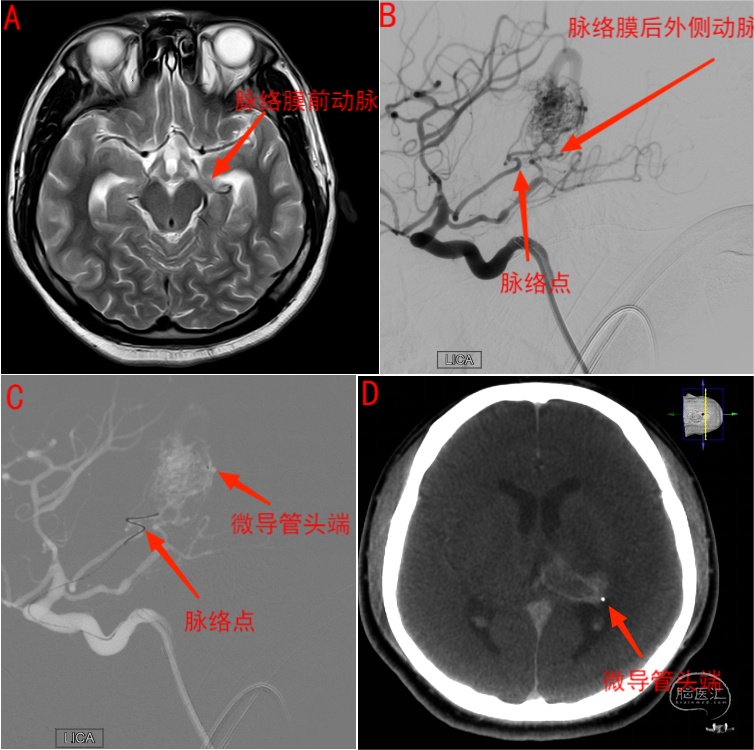

图15 左侧丘脑动静脉畸形伴出血患者。术前核磁T2像(A)显示左侧脉络膜前动脉增粗,左侧颈内动脉斜位造影(B)显示动静脉畸形由左侧脉络膜前动脉及脉络膜后外侧动脉供血,脉络点如图中所示。C显示术中微导管在微导丝支撑下越过脉络点并接近畸形团。D为术中XperCT证实微导管头端位于出血动静脉畸形团后外侧。